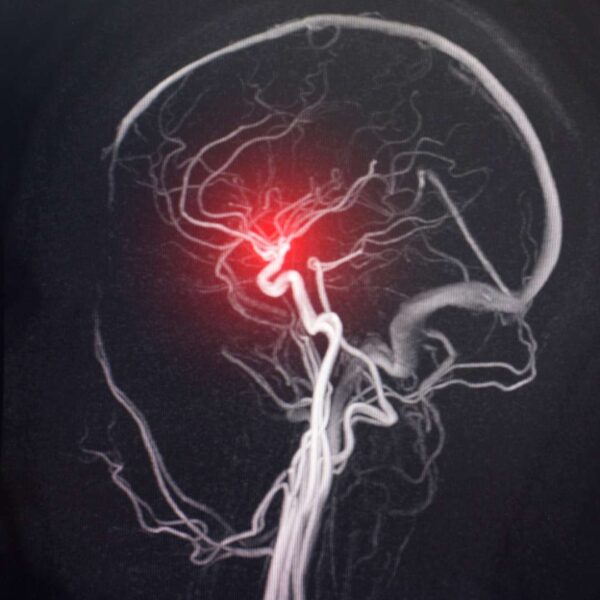

This common post-COVID symptom tends to be related to small arteries in the lungs not getting appropriate blood supply and having small micro clots. Specific interventions including Inositol,Cysteine, and NAC Supplements have been shown to break down these micro clots. The NLRPe stabilizer Resveratrol also treats inflammation here.